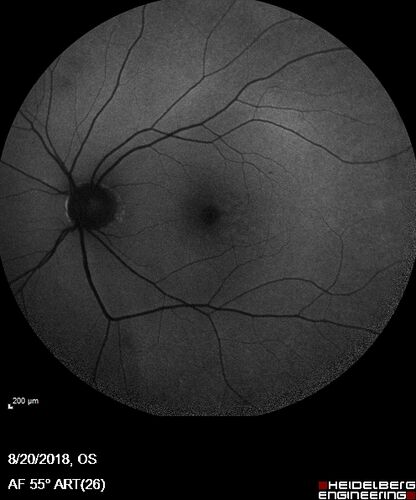

Large and Extensive Macular Drusen

64 year old female with 20/25 vision taking vitamins in for a checkup.